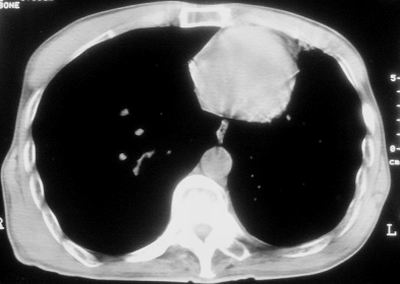

标题: CT11864:男,47岁,反复咳嗽、咯痰、咯血3年,请分析. [打印本页]

标题: CT11864:男,47岁,反复咳嗽、咯痰、咯血3年,请分析.

患者,男,47岁,反复咳嗽、咯痰、咯血3年,再发5天。痰培养未找到真菌、抗酸杆菌、癌细胞。

左肺上叶体积明显缩小,其内见多发透光区,纵隔向左侧移位,左肺下叶多发班片状病灶,边界模糊,1左肺上叶先天肺发育不全,2左肺下叶肺炎,

左肺上叶结核伴肺纤维化,纵隔移位,左肺下叶感染性病变,建议抗炎抗结核后复查,双肺气肿.

以下是引用xulianj在2008-2-25 21:01:00的发言:[br]左肺上叶结核伴肺纤维化有霉菌球形成,纵隔移位,左肺下叶感染性病变,建议抗炎抗结核后复查,双肺气肿.

考虑:左肺慢纤伴霉菌球形成、双肺全小叶型肺气肿。

1)考虑为:左肺上叶肺结核(空洞形成),伴左下肺感染;不排除霉菌感染可能。2)肺气肿。

左肺上叶结核伴肺纤维化空洞形成并左肺下叶感染,纵隔牵拉移位,建议作进一步检查排除左侧肺霉菌感染可能。